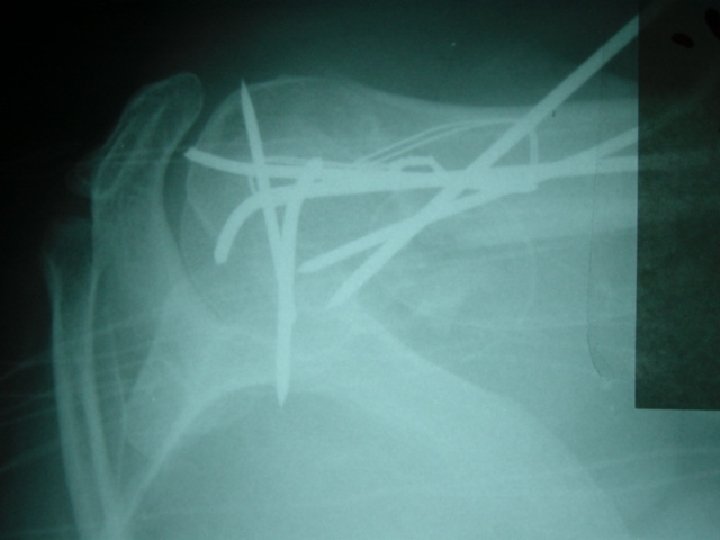

Open reduction 1 -displaced intra articular indications 2 -unstable Fr 3 -avulsion Fr 4

Open reduction 1 -displaced intra articular indications 2 -unstable Fr 3 -avulsion Fr 4 -Displaced pathologic Fr 5 - only operation indication 6 -Salter 3, 4 7 -compartment syn. 8 -NONUNION